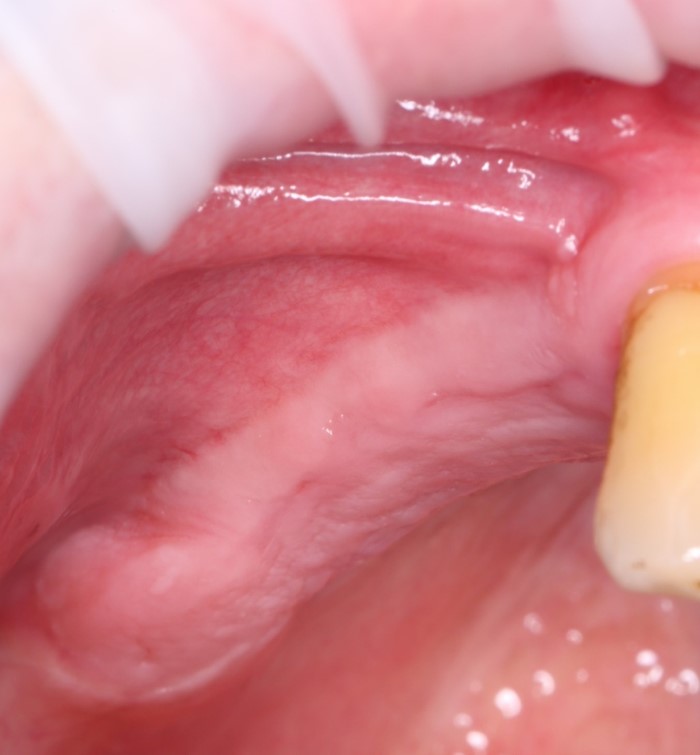

Поэтому после удаления зуба мы ждём, в общей сложности, около 4-8 недель, затем приступаем к имплантологическому лечению. Хотя, иногда бывают ситуации, когда мы делаем синуслифтинг одномоментно с удалением зуба, а сам имплантат ставим попозже:

через 4 месяца: